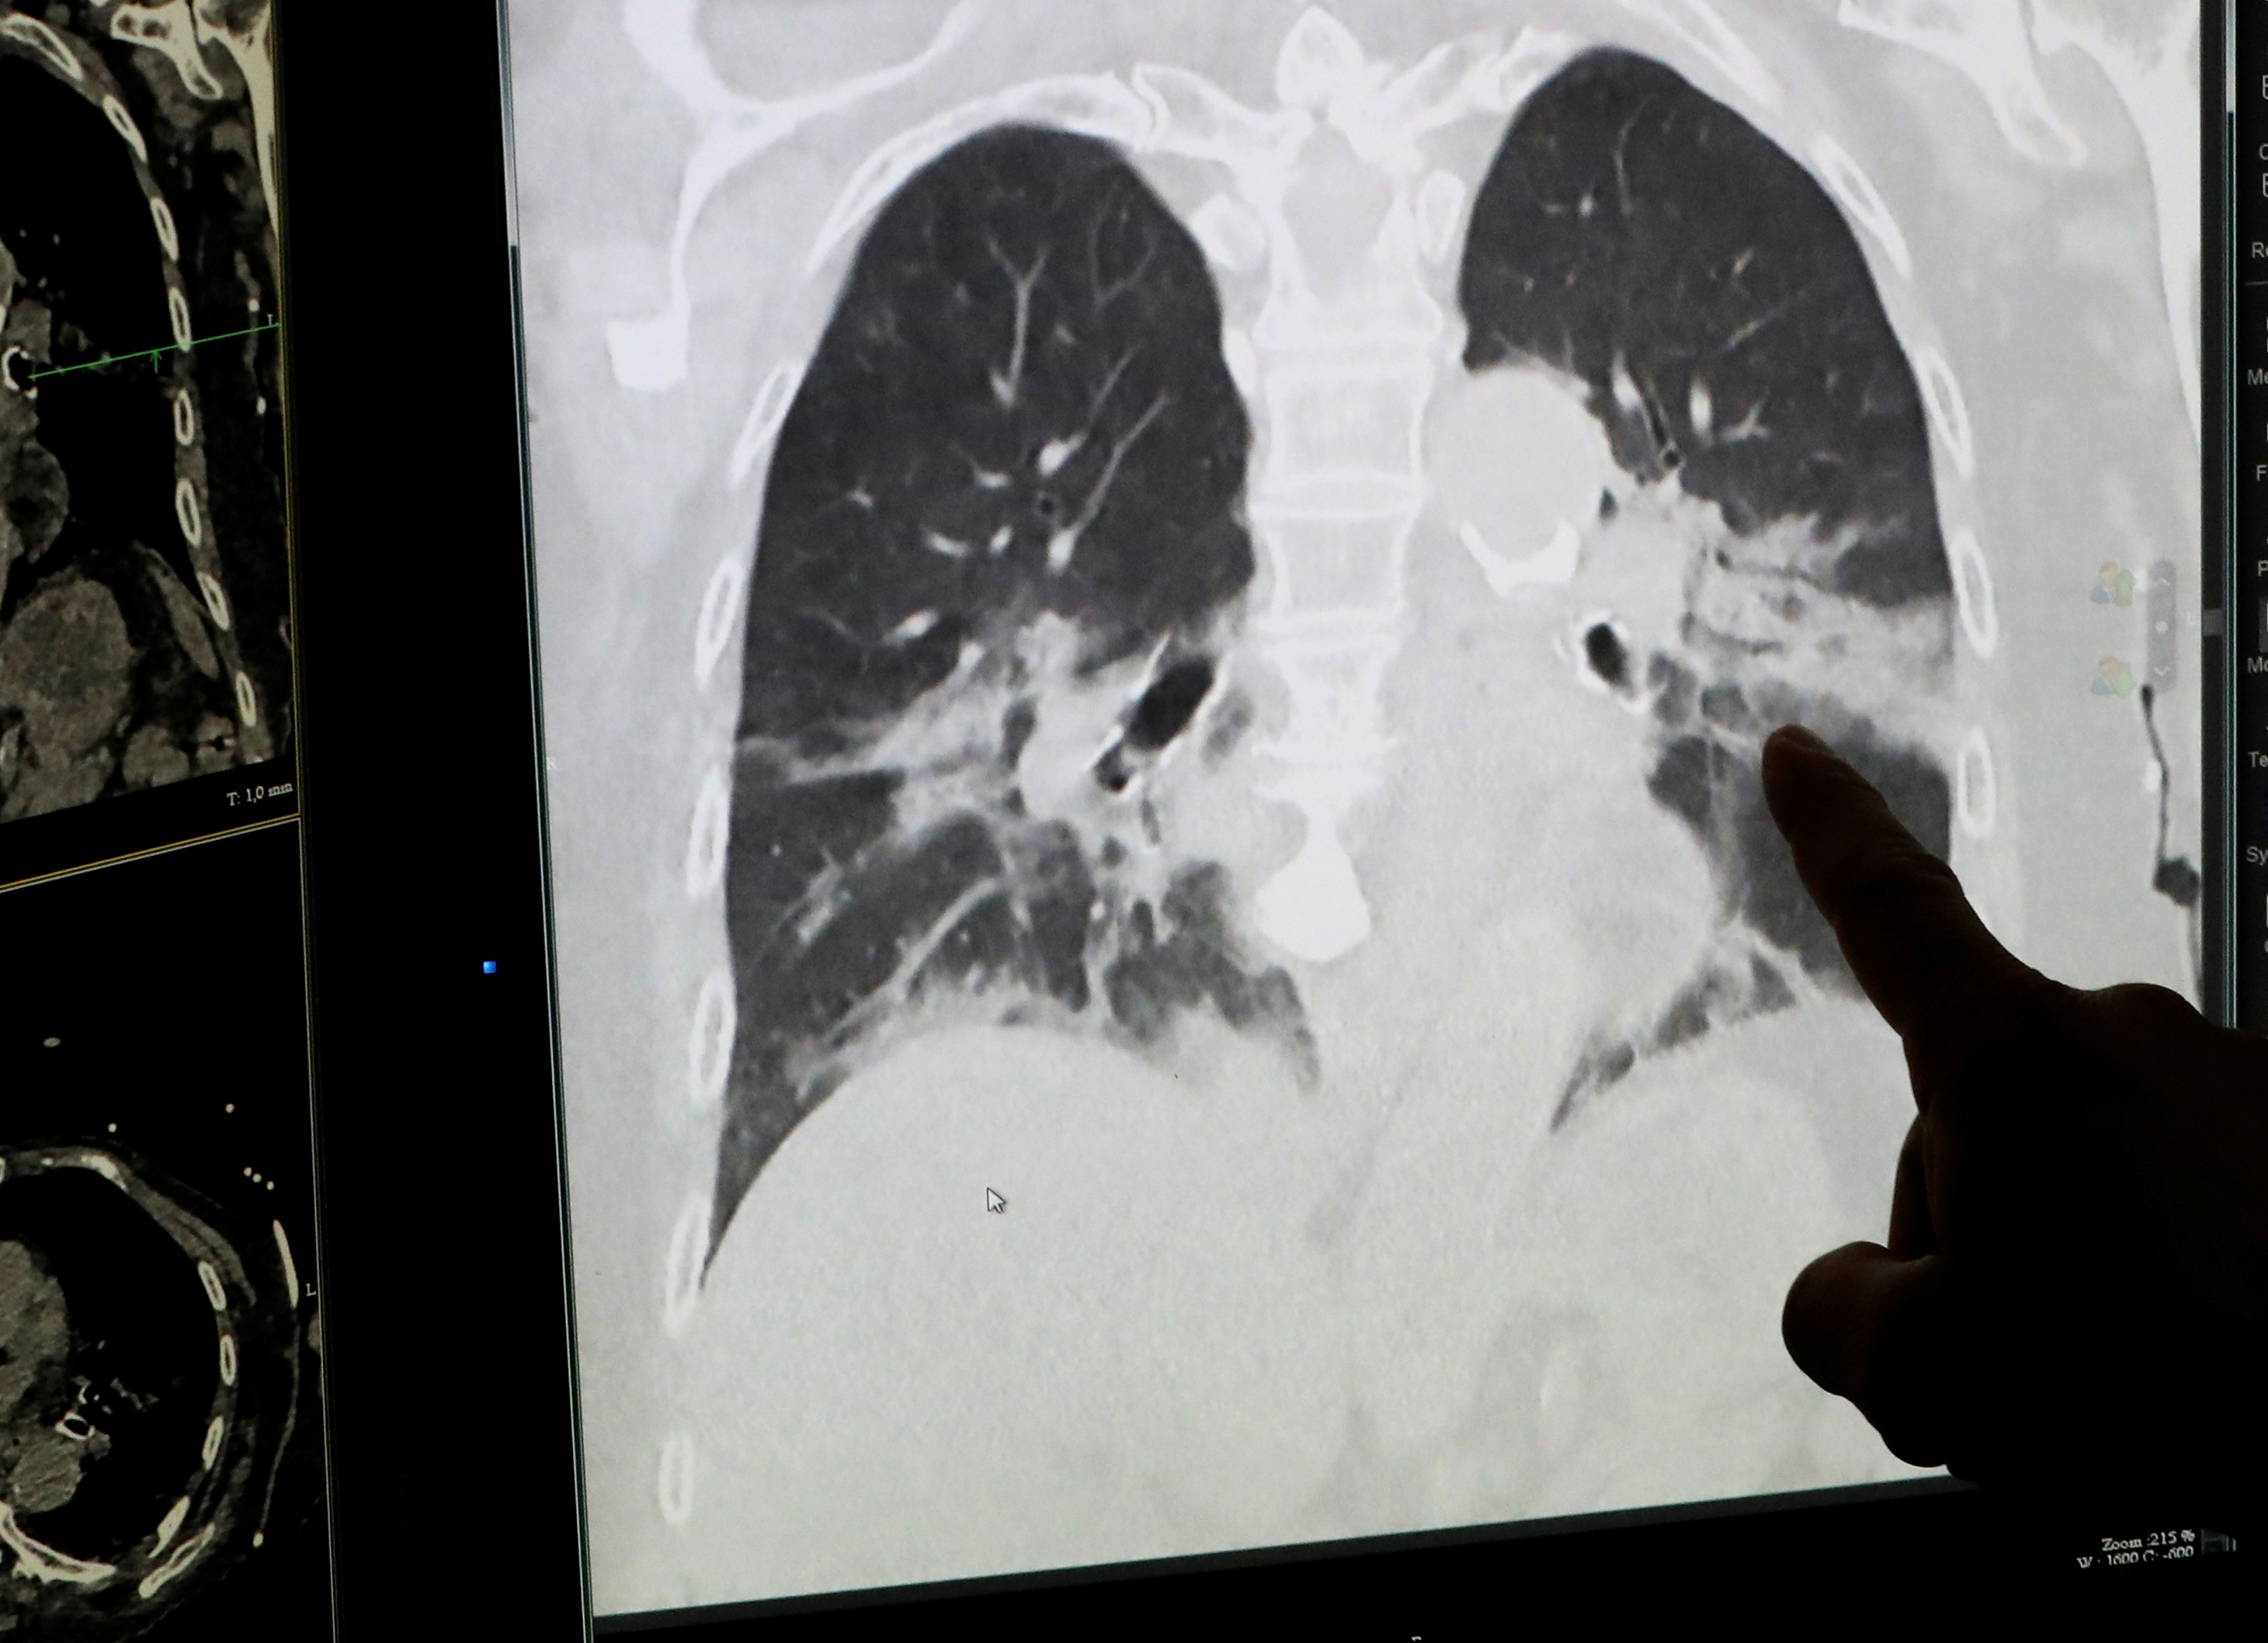

Поражение легких является одним из основных симптомов коронавируса (COVID-19). В данной статье представлены фото рентгеновских снимков, которые позволяют визуально оценить состояние легких при этом заболевании.

Матовое стекло коронавирус кт

На фотографиях рентгеновских снимков видно, как вирус воздействует на легочную ткань. Характерные признаки поражения легких включают пятна, инфильтраты и наличие жидкости внутри легочных альвеол.

Фото рентгеновских снимков помогают врачам и специалистам визуально определить степень поражения легких и принять соответствующие меры лечения и поддержки пациента.